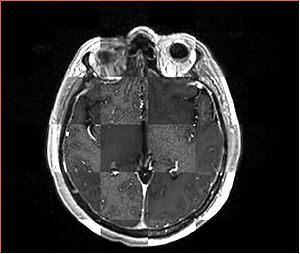

• Checkerboard appearance of unregistered images for the representative data of interest

• Case01